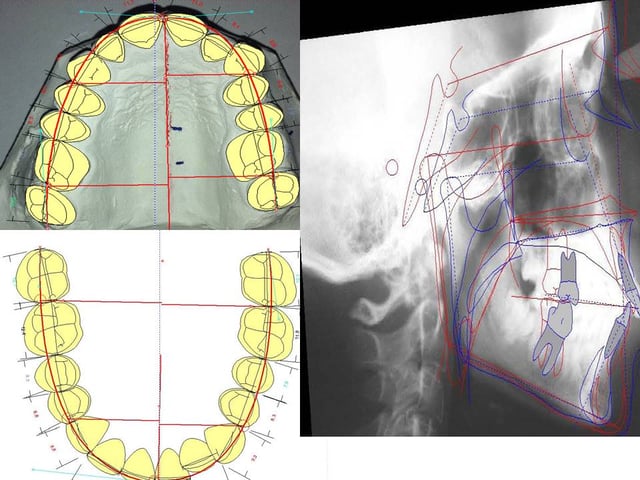

Radiografías

Las radiografías digitales necesarias para el tratamiento se realizan en nuestra Clínica Dental.

Mediante Ordenador

El análisis se realiza mediante un programa informático específico.